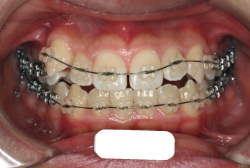

「前歯が重ならない」という主訴で来院したケースです。診断の結果、「重症の開咬」と判明しました。

この方の場合は、マルチブラケット装置は、歯の位置づけを3次元的に正確に行うことの出来る最善の矯正方法です。したがって開咬の治療も、形の改善としては問題なく行うことが出来ます。しかし、開咬が他の症状と少し違う点は、舌や唇の動かし方に問題があることから生じた症状なので、この問題を放置したまま形だけを作っても、時間が経つと簡単に後戻りしてしまうという問題です。つまり、マルチブラケット法で形態の矯正をするのと同時に、原因となっている筋肉の動きを正常に修正しなければなりません。この筋肉の動きを正常に修正する治療が、"筋機能訓練療法(Myo-functional therapy:略してMFT)"といわれるものです。

筋機能訓練療法は、筋機能訓練療法士という特別なトレーニングを積んだ歯科衛生士が行います。内容的には、いろいろなメニューがあり、簡単なものから始めて少しずつ筋肉の力を強めていき最終的には、無意識に起きる舌の突出をなくし、正しい摂食嚥下運動を獲得するまでトレーニングしていきます。この症例は、もちろん筋機能訓練にもしっかり取り組みました。治療後は開咬が改善しただけでなく、出っ歯の症状もなくなり唇の審美性が大幅に改善しました。もちろん奥歯の噛み合わせも正しい状態が確立しています。